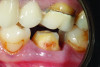

(4.) Pretreatment close-up retracted view of tooth No. 19 demonstrating a crown preparation with conventional retention and resistance form.

Figure 4

(5.) Delivery of a 3Y monolithic zirconia crown on tooth No. 19 with a resin-modified glass-ionomer cement.

Figure 5

Therefore, for crown preparations with "ideal" retention and resistance form, it is questionable whether bonding provides any further benefit. Moreover, bonding could be detrimental to the clinical outcome. In a scenario involving a well bonded 3Y or perhaps even 4Y monolithic zirconia crown of adequate thickness, given that the restoration is not likely to break or debond, the only other logical complications that may arise are biologic issues with the underlying tooth. Thus, a prudent clinician placing a highly fracture resistant zirconia crown on an ideal preparation would preferably deliver the restoration with a resin-modified glass-ionomer cement after it had been air abraded and treated with a zirconia primer (Figure 4 through Figure 6).